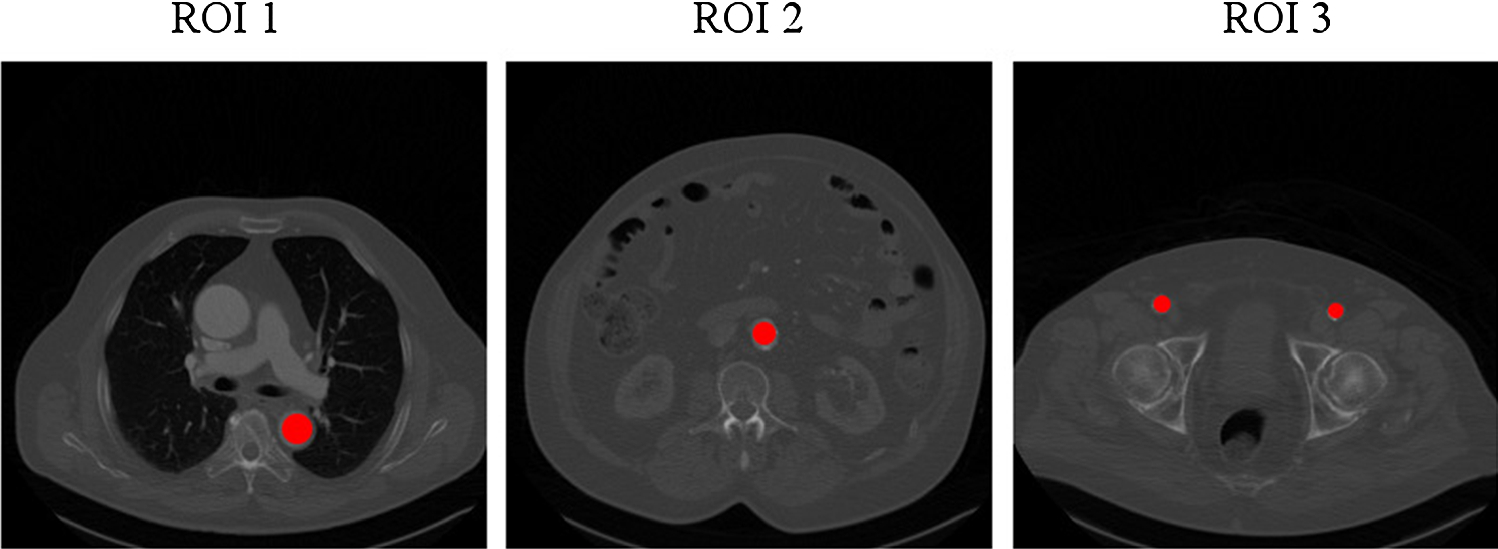

Fig. 2

Example of positioning ROI 1, 2 and 3 in the aorta and the arteria femoralis communis, respectively

In the standard procedure for contrast measurement for aortic CTA volumes three ROIs were manually positioned in axial CTA slices by radiologic experts (Fig. 2):

• ROI 1 Aorta, level: pulmonary artery bifurcation level.

• ROI 2 Aorta, level: kidneys.

• ROI 3 Arteria femoralis communis.

The ROIs were defined by the radiological experts of our team who were blinded to the to be labeled patients. The ROIs lie in axial slices which contain concise anatomical landmarks to provide good starting conditions for the proposed automatization. The rule-based classification assigns one of three classes, insufficient, optimal or excessive contrast to a patients CTA volume. The mean HU values of ROI 1, 2 and 3 were taken and each was assigned into one of the categories as presented in Table 1.